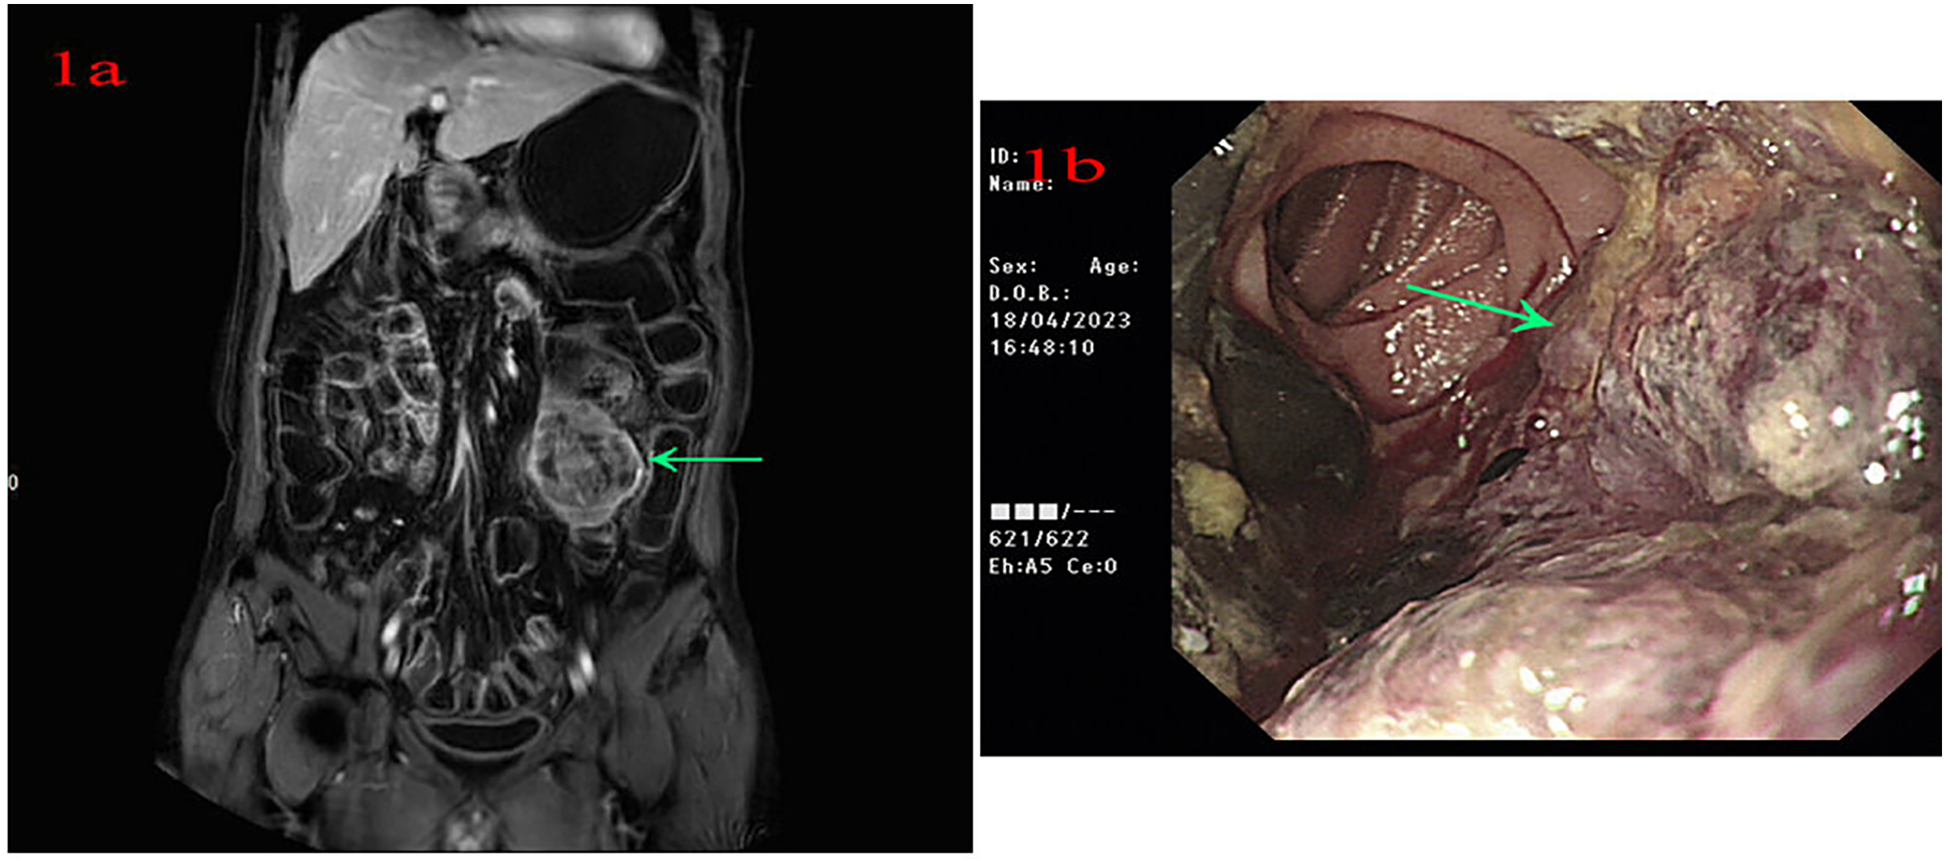

A 56-year-old male patient was admitted to Lanzhou University Second Hospital on 11 April 2023 because of intermittent melena for 1 month. The patient had visited a local clinic. Gastroscopy and colonoscopy were inconclusive and the patient received a blood transfusion. However, melena persisted; therefore, the patient was admitted to the Lanzhou University Second Hospital. The patient had no history of diabetes. A physical examination revealed a heart rate of 85 bpm, blood pressure of 125/77 mmHg, respiration rate of 16 bpm, and pale palpebral conjunctiva. A physical examination of the abdomen showed no abnormalities. The laboratory test results were as follows: white blood cells, 10.10 × 109/L; red blood cells, 3.36 × 1012/L; hemoglobin, 93 g/L; and platelets, 279 × 109/L. Tests for anti-HBs and anti-HBc were positive. Abdominal magnetic resonance imaging (MRI) indicated a left mid-abdominal mass and lymphoma with small bowel origin. Extraintestinal tumors or abdominal metastases were suspected (Figure 1a). Small bowel enteroscopy revealed infiltrating periannular ulcer lesions in the jejunum (Figure 1b). On 20 April 2023, surgery was performed, and an 8 cm intestinal tumor was found 50 cm away from the suspensory ligament of Treitz; another tumor (2 cm × 2 cm) was observed 130 cm away from the suspensory ligament of Treitz. A partial resection of the small intestine was performed (Figure 2a). The pathological examination revealed a mesenchymal, highly malignant, poorly differentiated sarcoma (Figure 2b). The patient was discharged 6 days postoperatively. After surgery, the patient received an anlotinib hydrochloride capsule (12 mg qd) orally for two cycles, after which a liver metastatic tumor was diagnosed, and peritoneal metastasis was also found subsequently. The patient died 6 months after surgery.

Figure 1

(a) Abdominal magnetic resonance imaging indicates a left mid-abdominal mass. (b) Small bowel enteroscopy shows infiltrating lesions of periannular ulcer at the jejunum.